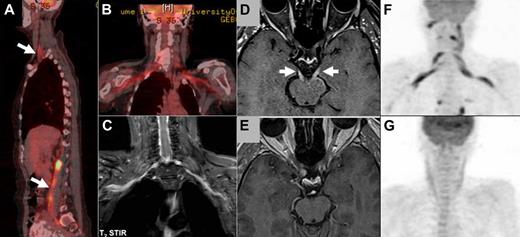

Imaging studies in NL. (A-B) FDG-PET imaging of a patient with neurolymphomatosis (NL). (A) Multiple sites of involvement, including the brachial and lumbosacral plexi (arrows). (B-C) Bilateral involvement of the brachial plexus in the same patient clearly detected by both FDG-PET (B) and by MRI (C) T2 short T1 inversion recovery imaging. (D-E) Enhanced MRI imaging (T1-weighted with gadolinium) of a patient with NL that affected multiple cranial nerves. (D) Bilateral abnormal enhancement of the oculomotor nerves that corresponded to the clinical presentation of bilateral ophthalmoplegia. (E) Complete resolution of abnormal enhancement after 2 cycles of treatment with intravenous high-dose methotrexate and intra-CSF treatment with cytarabine. These imaging findings matched the marked neurologic improvement observed under treatment. (F-G) FDG-PET imaging of a patient with NL who presented with severe painful sensorimotor neuropathy and bilateral brachial plexus involvement. (F) FDG-PET findings at diagnosis of NL compatible with bilateral brachial plexus involvement by lymphoma. (G) Complete resolution of abnormal tracer uptake after 2 courses of treatment with systemic high doses of methotrexate and cytarabine. The treatments lead to clear neurologic improvement and good control of the painful neuropathy.

All patients were evaluated by imaging and 23 (46%) were assessed by more than one modality. Magnetic resonance imaging (MRI) was done in 47 (94%) cases whereas 18F-fluoro-2-deoxy-D-glucose (FDG) positron emission tomography–computed tomography (PET-CT) was performed in 19 (38%) patients, the majority (16; 84%) attained in patients diagnosed after 2004. The diagnostic yield of MRI and FDG-PET was high (Table 2), with abnormal findings found in 77% and 84%, respectively. MRI findings were detailed in 41 of 47 (87%) patients and included abnormal enhancement of the affected neural structure in 31 (76%) cases. The affected nerves were most commonly characterized as thickened (22 of 41; 53%), in 7 (17%) the involvement was diffuse, and in 12 (30%) it was nodular. Despite the high yield of imaging evaluation, the findings were often not definitive and consequently nerve biopsy was performed in 26 (52%) patients. The biopsy demonstrated NL in 23 (88%) patients. Biopsy was performed from cranial nerves (2 cases), L2 spinal nerve root (1), brachial plexus (1), and peripheral nerves (15), including sciatic, peroneal, sural, femoral, and median nerves. Of the 5 sural nerve biopsies, 3 were negative, whereas all other biopsies demonstrated neural infiltration by malignant cells. For 7 patients, the site of biopsy was not specified.

The response to treatment was assessed by comparing the pretreatment and posttreatment scores of ECOG-PS, neurologic function score, report of neurologic status, and objective response as detected by imaging. Of the 47 treated patients, pretreatment and posttreatment evaluations were available as follows: ECOG-PS and neurologic function in 35 patients, detailed neurologic status in 28 cases, and imaging in 25 patients. Response to treatment based on 35 pretreatment and posttreatment evaluations was noted in 16 (46%) patients who presented with a complete or partial resolution of their symptoms and signs. An additional 9 (26%) patients stabilized on treatment, and the remaining 10 patients progressed despite treatment. The median ECOG-PS changed from 2 (pretreatment) to 1.5 (posttreatment) and median neurologic function score from 2 to 1. These changes were not statistically significant (paired t test). Posttreatment imaging demonstrated complete resolution of the previously documented abnormalities related to NL in 14 (56%) of 25 patients (Figure 1D-G), partial response in another 3 (12%) cases, 1 patient showed no change, and 7 (28%) worsened. Objective response as demonstrated by imaging corresponded to clinical and neurologic improvement in all 17 patients.

Of all diagnostic tools, imaging studies are of the greatest clinical utility. All our patients were evaluated by one or more imaging techniques, the majority (94%) by MRI. MRI reveals nerve or root enlargement with or without contrast enhancement and often involvement of neural plexus (brachial or lumbar) that is more difficult to detect1,7-14 (Figure 1C). MRI findings are not specific for NL and might sometimes be seen in acute or chronic inflammatory radiculoneuropathies, in neurofibromatosis, in inflammatory pseudotumor, and in malignant tumors of the peripheral nerve sheath. Interpretation of imaging studies in the context of clinical manifestations and laboratory studies is necessary. MRI yields abnormal findings in almost 80% of affected patients (Table 2) and facilitates the diagnosis, particularly when a history of hematologic malignancy is known.

PET-CT appears to be a highly sensitive diagnostic method facilitating identification of NL based on our experience and that reported in the literature (group B, Table 2; Figure 1A,B,F). Altogether, the reported experience is of 40 NL patients evaluated by PET-CT, among whom 87.5% were positive studies. Although the total number of reported cases diagnosed by PET-CT is still small, positive findings are highly suggestive of the diagnosis of NL, particularly in patients with a known history of hematologic malignancy. Together with MRI findings, PET-CT may define the best target for a biopsy, if one is indicated, especially in the instance of primary NL.

Clinical improvement (functional recovery, reduction of pain) and radiographic resolution (improvement of nerve root enlargement and enhancement or normalization of FDG-PET uptake) have been observed in 50% to 70% of treated patients (Table 2; Figure 1D-G). Standardized criteria to measure response are not available; therefore, no recommendations can be made regarding treatment response.